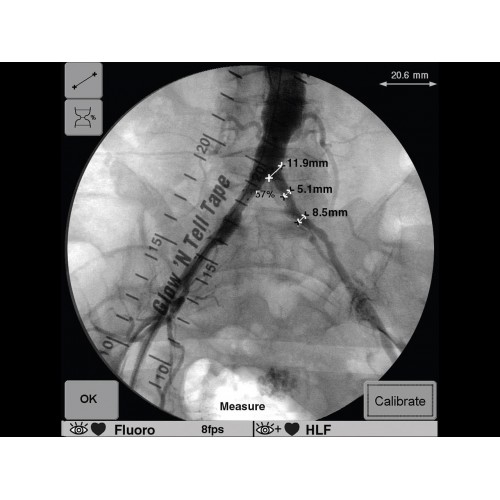

Инновационная мобильная С-дуговая система для интраоперационной визуализации с высоким разрешением. Обеспечивает хирургов качественным изображением в реальном времени при минимальной лучевой нагрузке. Усовершенствованная эргономика позволяет легко позиционировать аппарат в условиях операционной. Поддерживает интеграцию с современными хирургическими навигационными системами.

Передовая рентгенохирургическая система GE OEC 9900 Elite представляет собой инновационное решение для проведения широкого спектра малоинвазивных вмешательств. Это оборудование премиум-класса сочетает высочайшее качество визуализации с интуитивно понятным управлением, устанавливая новые стандарты в области интраоперационной рентгеноскопии.

GE OEC 9900 Elite оснащен революционной системой визуализации, обеспечивающей кристально четкое изображение анатомических структур. Интеллектуальная система автоматически адаптирует параметры исследования под конкретную хирургическую задачу, обеспечивая оптимальный баланс между качеством изображения и лучевой нагрузкой. Особое внимание уделено удобству работы операционной бригады.

В операционной практике GE OEC 9900 Elite демонстрирует исключительную эффективность при проведении сложных малоинвазивных процедур. Оборудование позволяет значительно сократить время вмешательства и повысить его безопасность для пациента. Многие хирурги отмечают улучшение точности операций и комфорт работы с системой.